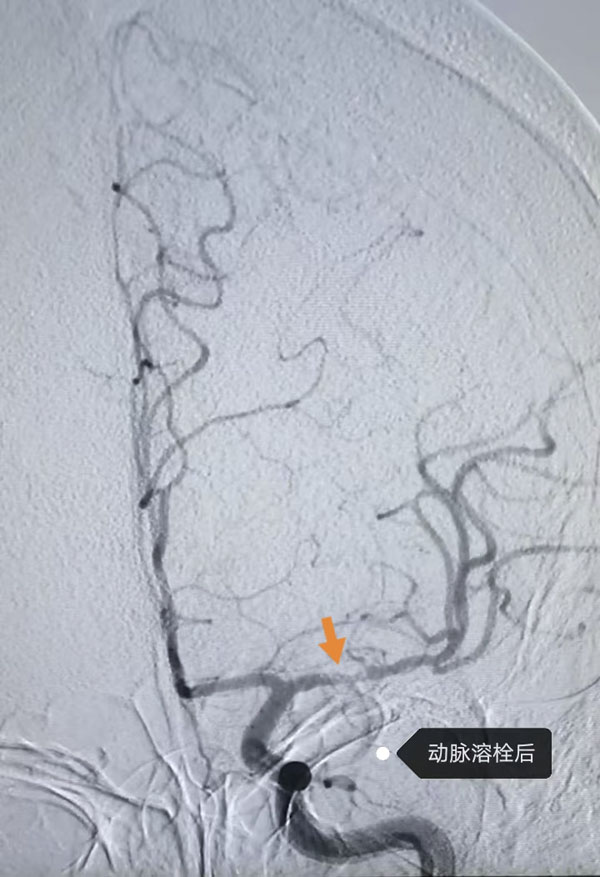

鉴于患者病情危急,接诊医生李晨曦紧急联系介入组李彦青医生启动卒中救治流程,在介入手术室的人员的帮助下,为其实施脑动脉造影术。术中,李彦青发现患者此次发病的责任血管“左侧大脑中动脉”虽存在血流再通,但局部仍为重度狭窄且血栓负荷重,遂决定通过左侧颈内动脉给药以改善局部血供。给药后,复查造影显示狭窄程度明显改善。术后,患者NIHSS评分(神经功能缺损评分)由入院时的8分快速降至3分,言语及右侧肢体活动不利明显改善。一周后出院时,评分进一步降至1分,言语及肢体活动基本恢复正常。